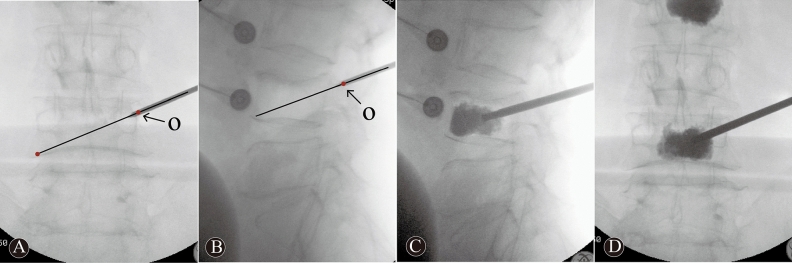

Figure 2.

A 68 years-old woman in O-PKP group with L1, L2 and L4 OVCFs. These intraoperative images demonstrate operation techniques and procedures. The needle via point “O” to the contralateral inferior corner of vertebral body on posteroanterior imaging (A). The entry point “O” is located at the intersection of the posterior-superior margin of the pedicle and lateral margin to superior articular process on lateral imaging (B). These images (C, D) demonstrate an ideal bone cement distribution, the bone cement across the anterior one-third midline and across the midline of the vertebral body.

The O-PKP group: The O-PKP used a modified unilateral extrapedicular puncture approach. The bone entry point was the intersection between the base of the transverse process, the posterior-superior margin of the pedicle, and the lateral margin of the superior articular process. This entry point was defined as the “O” point (as this point was similar to the coordinate origin), as shown in Fig. 1A–C. Once the puncture needle reached the “O” point, it was close to the superior margin of the pedicle and was lateral to the superior articular process on lateral imaging (Fig. 2B). The puncture angle was adjusted such that the puncture needle entered the “O” point and the vertebral midpoint to the contralateral inferior corner of the vertebral body (Fig. 2A). The needle was then inserted slowly, using the anterior one-third midpoint of the vertebral body, as shown on lateral imaging, as the needle target. Posteroanterior imaging indicated that the needle had reached the vertebral midline. Lastly, a balloon was embedded in the vertebral body, and bone cement was then injected into the fractured vertebral body (Fig. 2C, D).